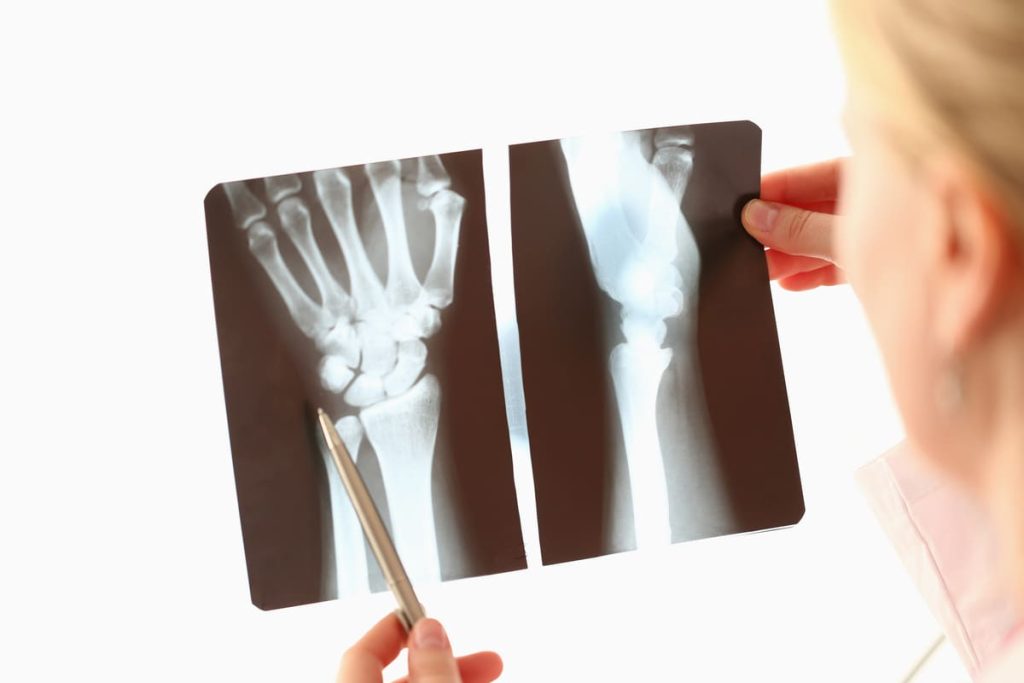

We are committed to delivering outstanding emergency care, with a strong focus on rapid and effective treatment. Our team uses state-of-the-art technologies and advanced techniques to ensure the best possible outcomes.

Comprehensive management of hand and upper limb emergencies.

Emergency consultations: Rapid assessment of hand and upper limb injuries.

Surgical procedures: Emergency treatment of fractures, dislocations, and tendon injuries.